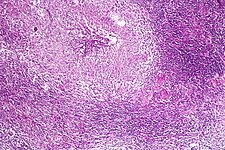

Pulmonary tuberculosis characterized by granulomatous inflammation with necrotizing epithelioid granulomas. Low power view. H&E stain.

Pulmonary tuberculosis featuring necrotizing granulomas, H&E stain.

Pulmonary tuberculosis featuring necrotizing granulomas, high power view, H&E stain.